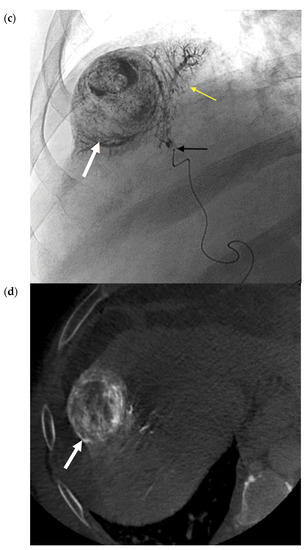

- Riaz, A.; Gates, V.; Atassi, B.; Lewandowski, R.; Mulcahy, M.F.; Ryu, R.K.; Sato, K.T.; Baker, T.; Kulik, L.; Gupta, R.; et al. Radiation Segmentectomy: A Novel Approach to Increase Safety and Efficacy of Radioembolization. Int. J. Radiat. Oncol. 2011, 79, 163–171. [Google Scholar] [CrossRef]

- Padia, S.A.; Kwan, S.W.; Roudsari, B.; Monsky, W.L.; Coveler, A.; Harris, W.P. Superselective Yttrium-90 Radioembolization for Hepatocellular Carcinoma Yields High Response Rates with Minimal Toxicity. J. Vasc. Interv. Radiol. 2014, 25, 1067–1073. [Google Scholar] [CrossRef] [PubMed]

- Lewandowski, R.; Gabr, A.; Abouchaleh, N.; Ali, R.; Al Asadi, A.; Mora, R.; Kulik, L.; Ganger, D.; Desai, K.; Thornburg, B.; et al. Radiation Segmentectomy: Potential Curative Therapy for Early Hepatocellular Carcinoma. Radiology 2018, 287, 1050–1058. [Google Scholar] [CrossRef]